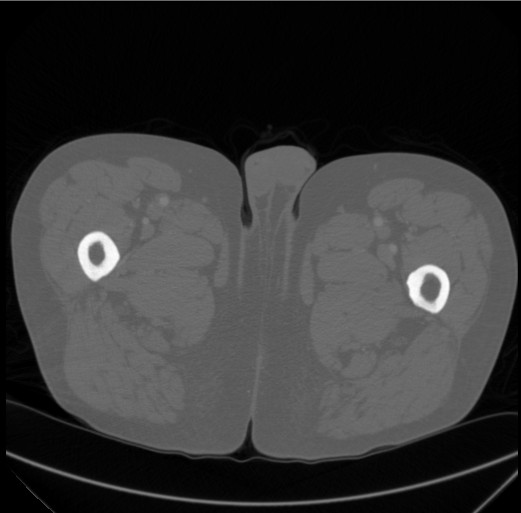

图2.正确的映射,dicom显示在IrfanView中